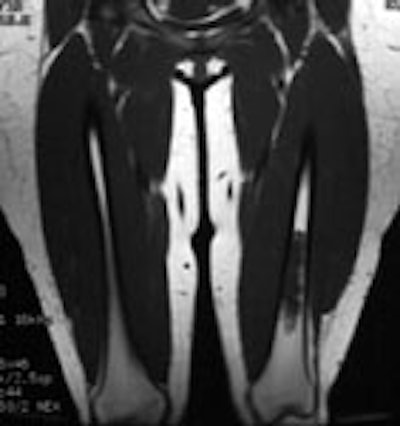

Ewings sarcoma of the pelvis: The bone scan demonstrates extensive, intense tracer uptake involving the left iliac wing, extending into the ischium and left sacrum. CT scan revealed a mixed, but predominantly sclerotic lesion involving the bone with an associated soft tissue mass. Note that the sacrum fails to demonstrate a CT abnormality. The T2 weighted images from the patients MR exam more clearly defines the lesion. Sacral involvement is clearly evident (white arrows) and there is also a large soft tissue component. |